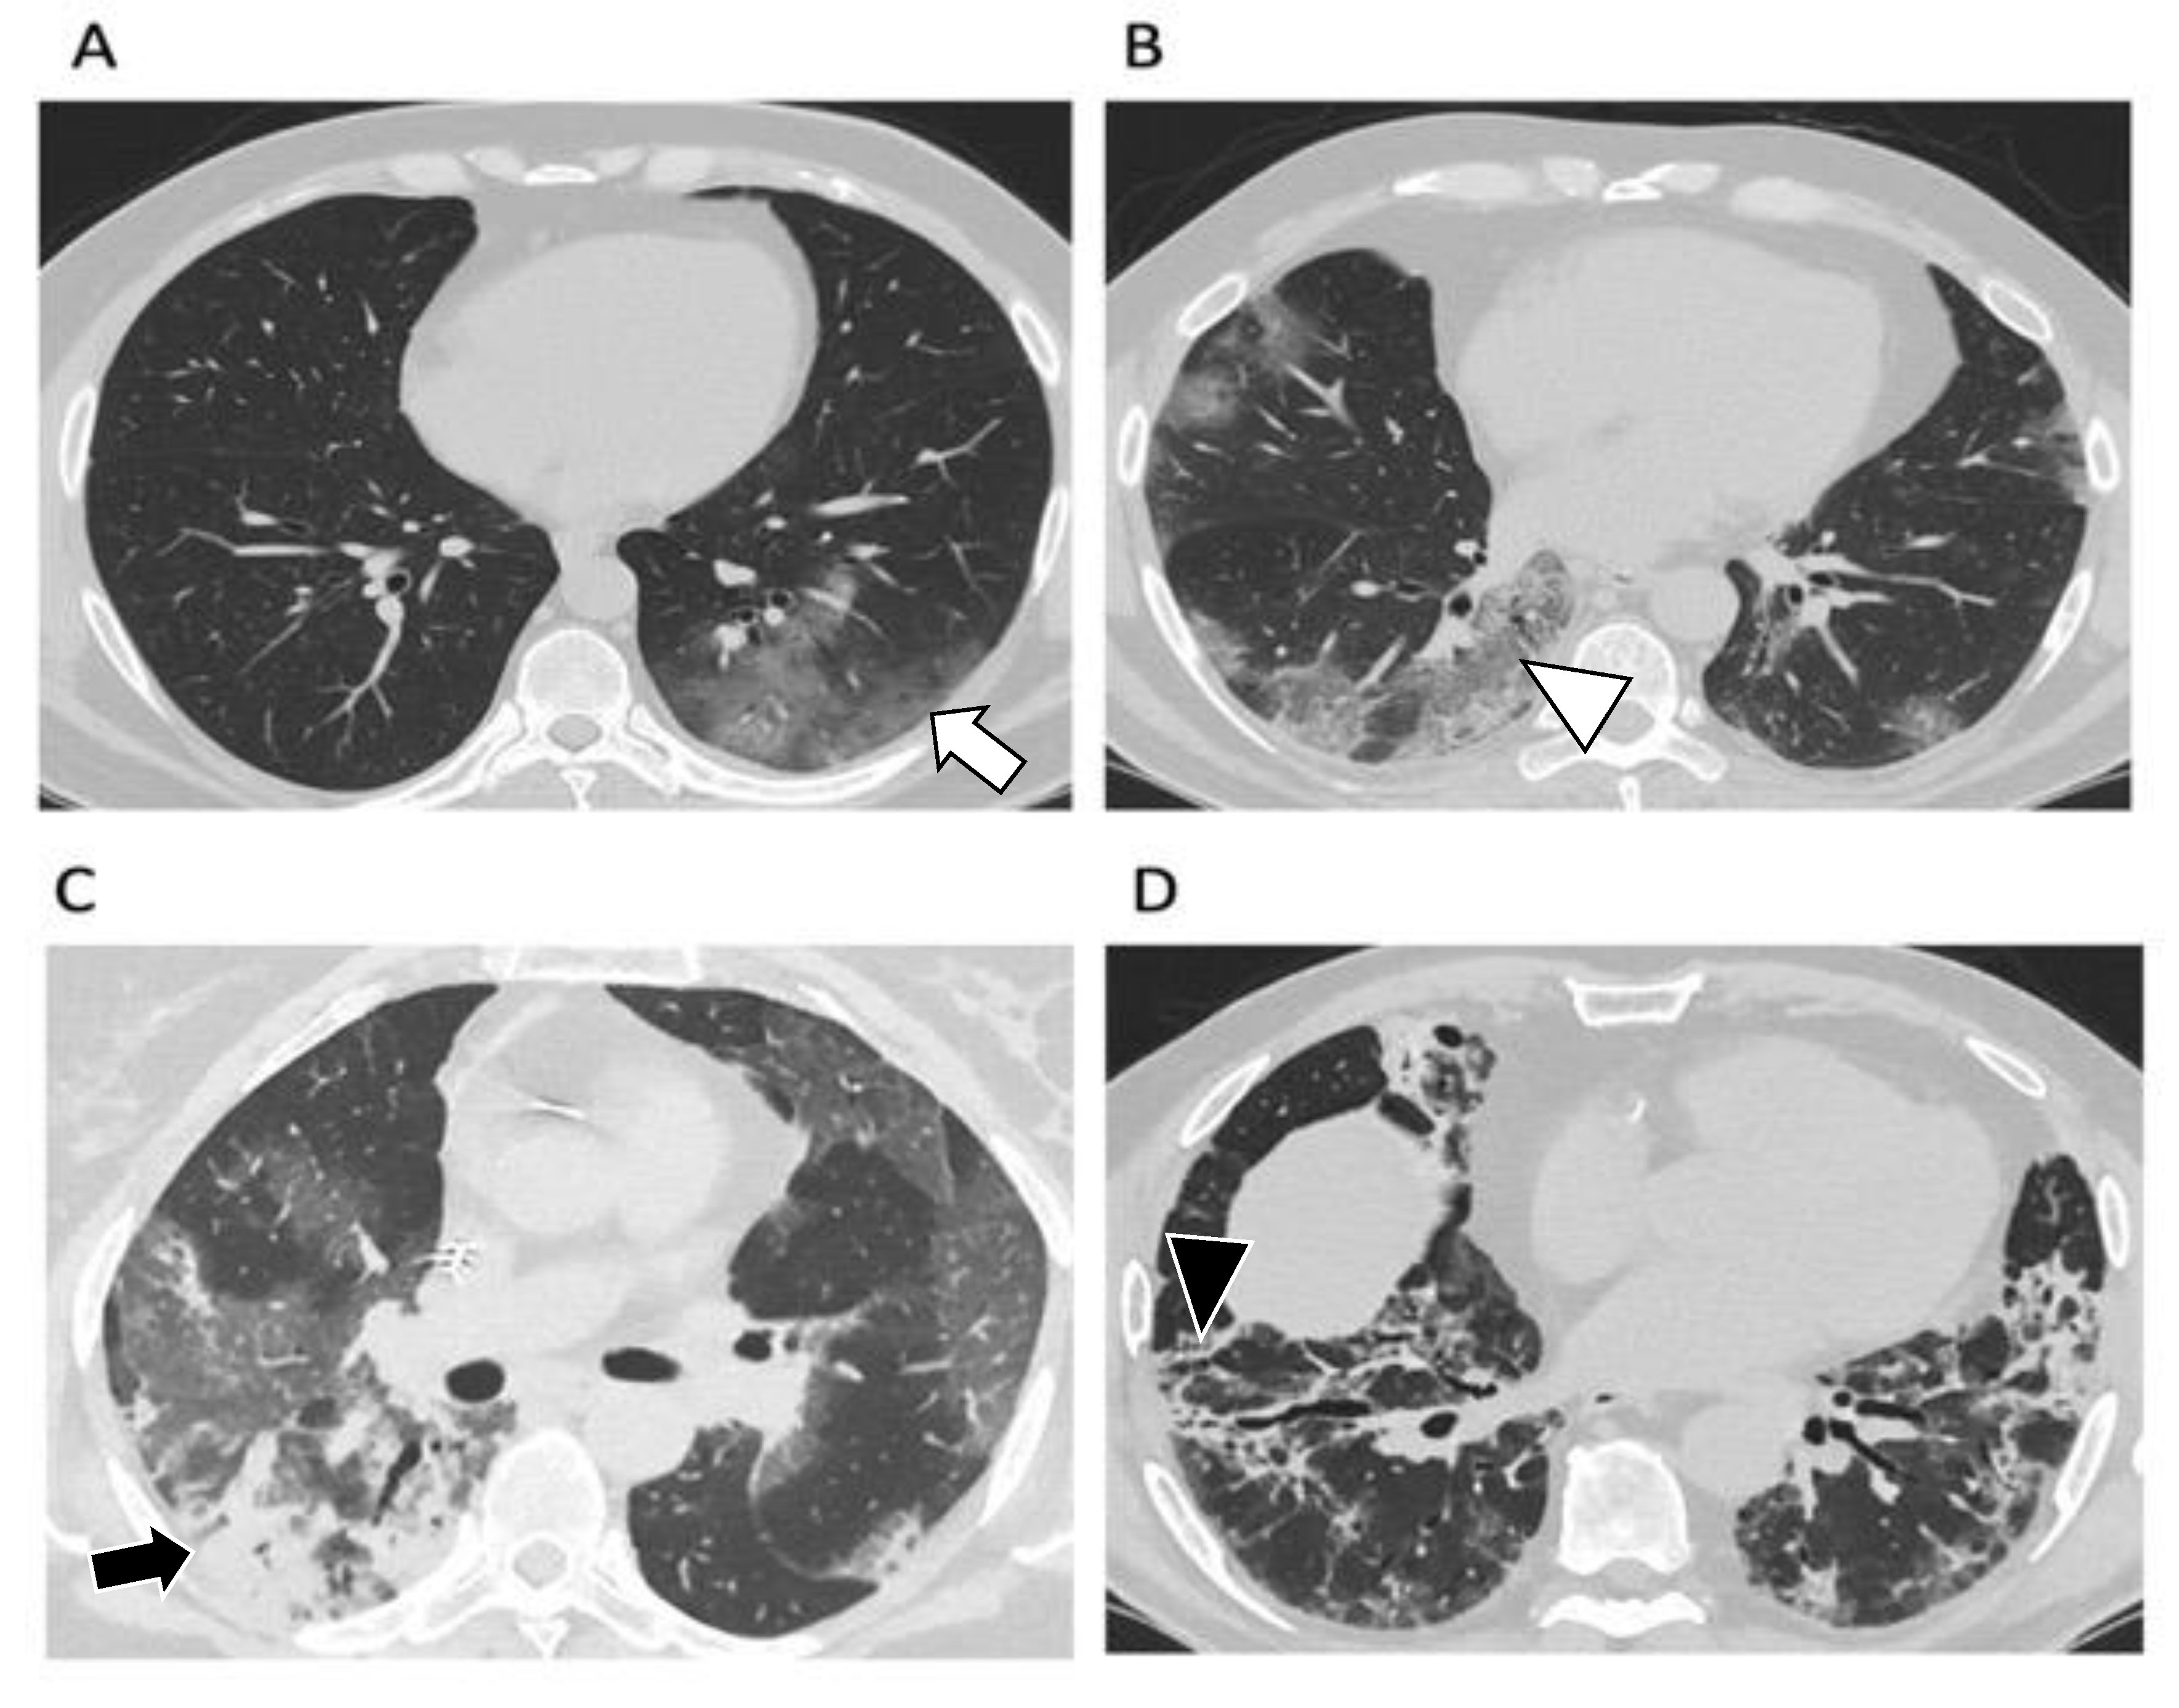

Four stages on CT have been described [23,24]: early/initial (0–4 days) characterized by normal CT or GGO only; progressive (5–8 days) with increased GGOs and crazy paving appearance; peak (9–13 days) characterized by lung consolidation and absorption stage (>14 days) with the appearance of fibrotic changes (Figure 2).

Figure 2.

Axial chest CT images with windowing and leveling for the evaluation of lung parenchyma in patients affected by SARS-CoV-2 according to the different stages of the disease. (A). Early or initial stage (0–4 days): normal CT or sporadic ground-glass opacities (white arrow). (B). Progressive stage (5–8 days): ground-glass opacities are widely distributed, and crazy paving appearance can be evident (white arrowhead). (C). Peak stage (9–13 days): lung consolidations (black arrow) appear nearby the ground-glass opacities. (D). Absorption stage (>14 days): consolidations and ground-glass opacities slowly disappear while fibrotic findings can be evident, especially in the peripheral and lower zones (black arrowhead).

Lung damage is maximal at around day 10 and then generally decreases progressively in size and attenuation value [25].

Lung abnormalities on CT may persist beyond one month in up to 98% of patients, particularly in those with initial severe lung disease at baseline [24]. Nevertheless, the long-term sequelae of COVID-19 and the associated lung abnormalities remain uncertain.